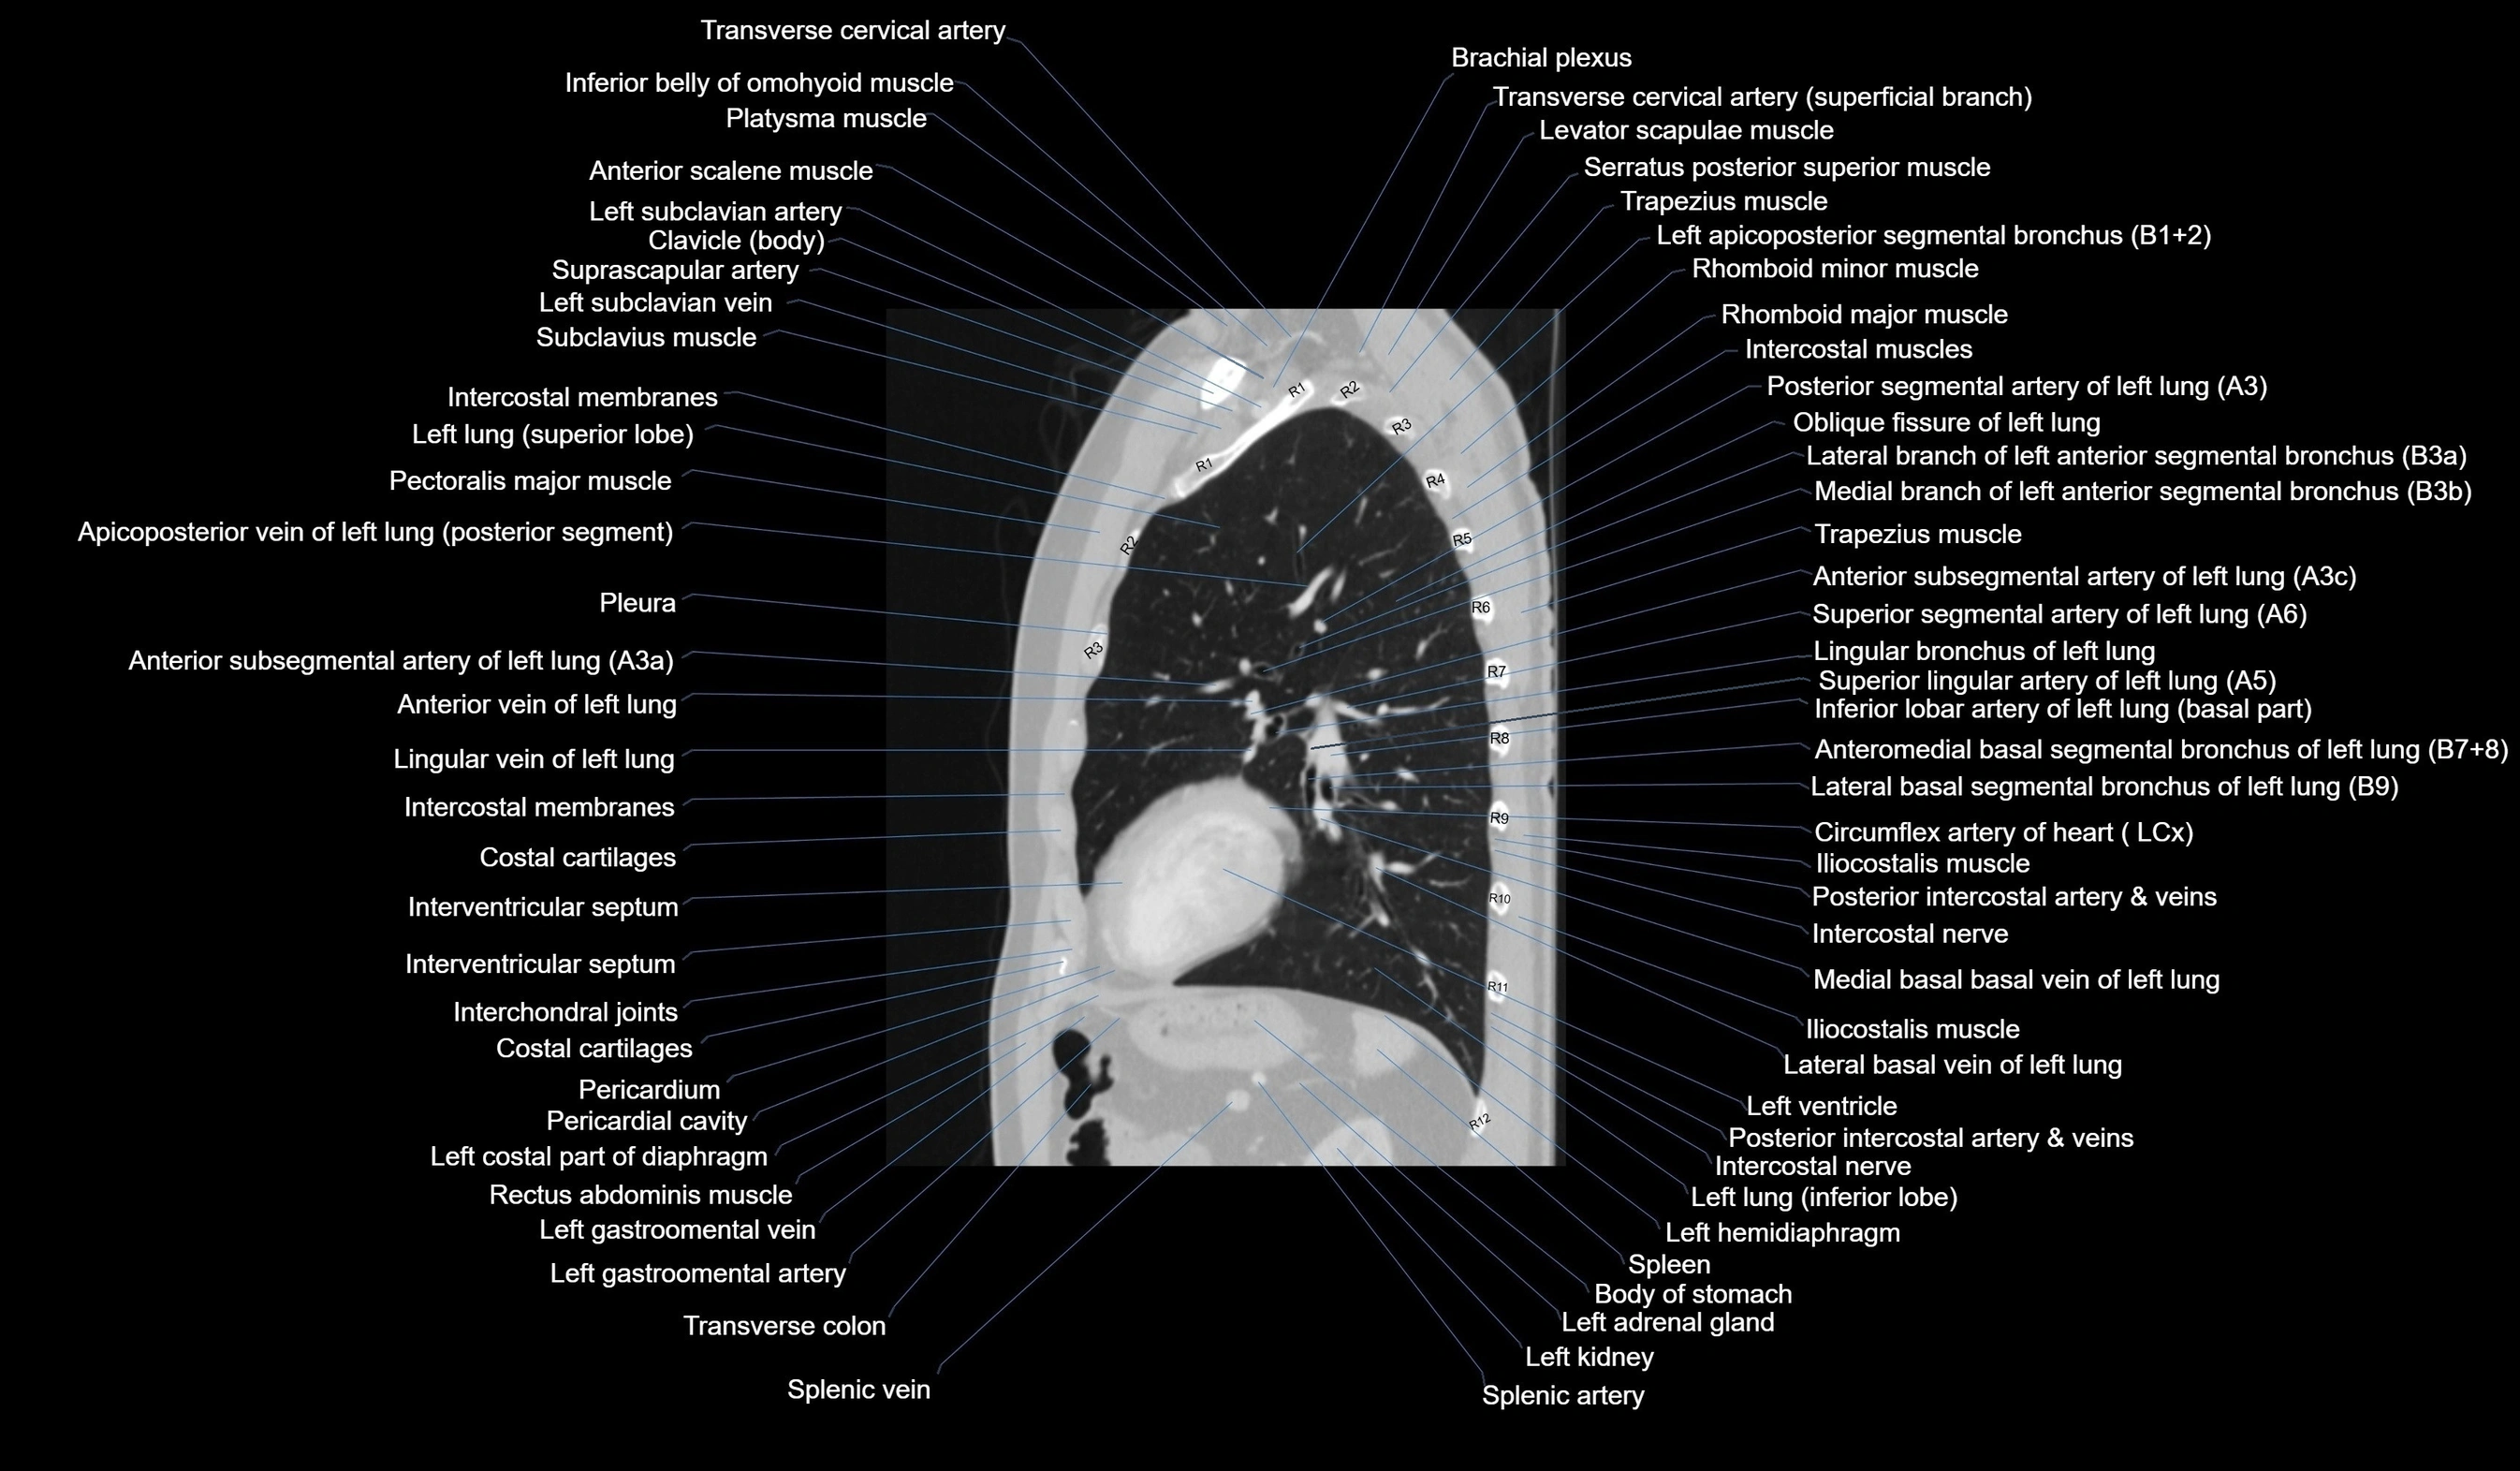

- Anterior basal segmental artery of left lung

- Anterior basal vein of left lung

- Anterior segmental artery of left lung

- Anterior vein of left lung

- Anteromedial basal bronchus of left lung (B7+8)

- Circumflex artery (LCx)

- Costal cartilages

- Descending colon

- Interventricular Septum

- Left adrenal gland

- Left costophrenic angle

- Left gastro-omental (gastroepiploic) vein

- Left hemidiaphragm

- Left lung (inferior lobe)

- Lingular vein of left lung

- Oblique fissure of left lung

- Pericardial cavity

- Pericardium

- Pleura

- Rectus abdominis muscle

- Spleen

- Splenic artery

- Splenic vein

- Thoracic part of esophagus

- Transverse colon